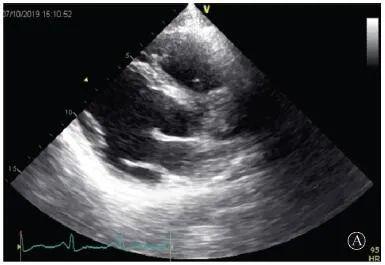

患者入院后無特殊不適,心率70次/min,血壓110/60 mmHg,心功能Ⅱ級。查血常規(guī):血紅蛋白139 g/L,白細胞7.39×109/L,血小板221×109/L。尿常規(guī)、便常規(guī)+潛血均正常。生化:丙氨酸氨基轉移酶38 U/L,白蛋白47 g/L,鉀3.9 mmol/L,肌酐(酶法)65 μmol/L,總膽固醇3.52 mmol/L,低密度脂蛋白膽固醇2.08 mmol/L。CK:1256→487 U/L,CK-MB 9.7→3.8 μg/L,cTnI 85.90→68.50 pg/ml。N末端B型利鈉肽原70 pg/ml。CK同工酶電泳:肌酸激酶MM質量100.0%(此時CK-MB已正常)。血沉1 mm/第1小時,高敏C反應蛋白1.61 mg/L;補體:C3 0.876 g/L,C4 0.174 g/L。免疫球蛋白:IgG 9.52 g/L,IgA 1.73 g/L,IgM 0.62 g/L。血清蛋白電泳未見M蛋白。糖化血紅蛋白5.1%。乳酸(運動前)1.1 mmol/L,乳酸(運動中)6.6 mmol/L,乳酸(運動后)7.8 mmol/L。肌炎抗體譜:抗PM-SCL75(+),余均(-)。心電圖:aVL、V5、V6導聯(lián)T波倒置(圖2)。冠狀動脈CT未見明顯異常。超聲心動圖:左室舒張末內(nèi)徑55 mm,左室收縮功能減低,心尖部、左室壁普遍運動減低,以左室下后壁為著,左室下后壁肌小梁明顯增多可見隱窩,疏松層與致密層之比為1.7;左室射血分數(shù)(雙平面)45%;右冠狀動脈開口6.5 mm,開口處未見明確瘤樣擴張(圖3)。

A:胸骨旁長軸平面,左室舒張末內(nèi)徑略增大,室壁無明顯增厚;